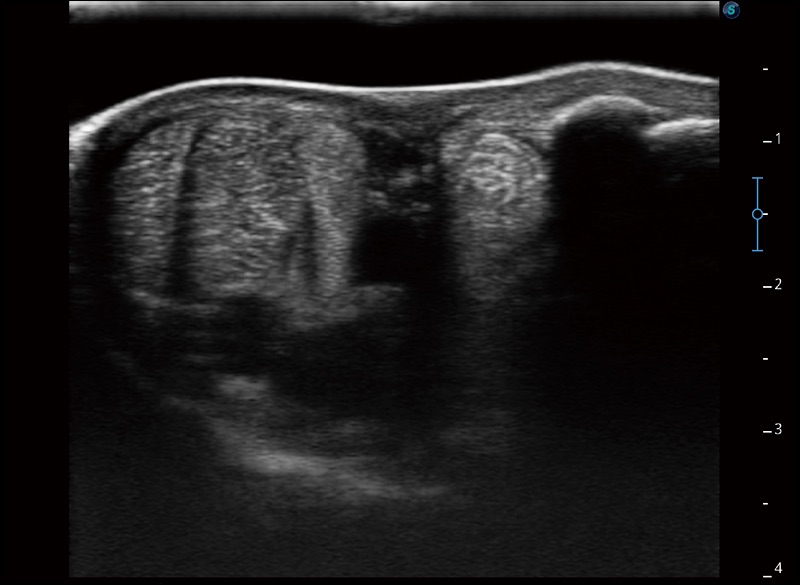

扩展成像

支持线阵和凸阵探头,一键操作即可获得更宽的图像视野